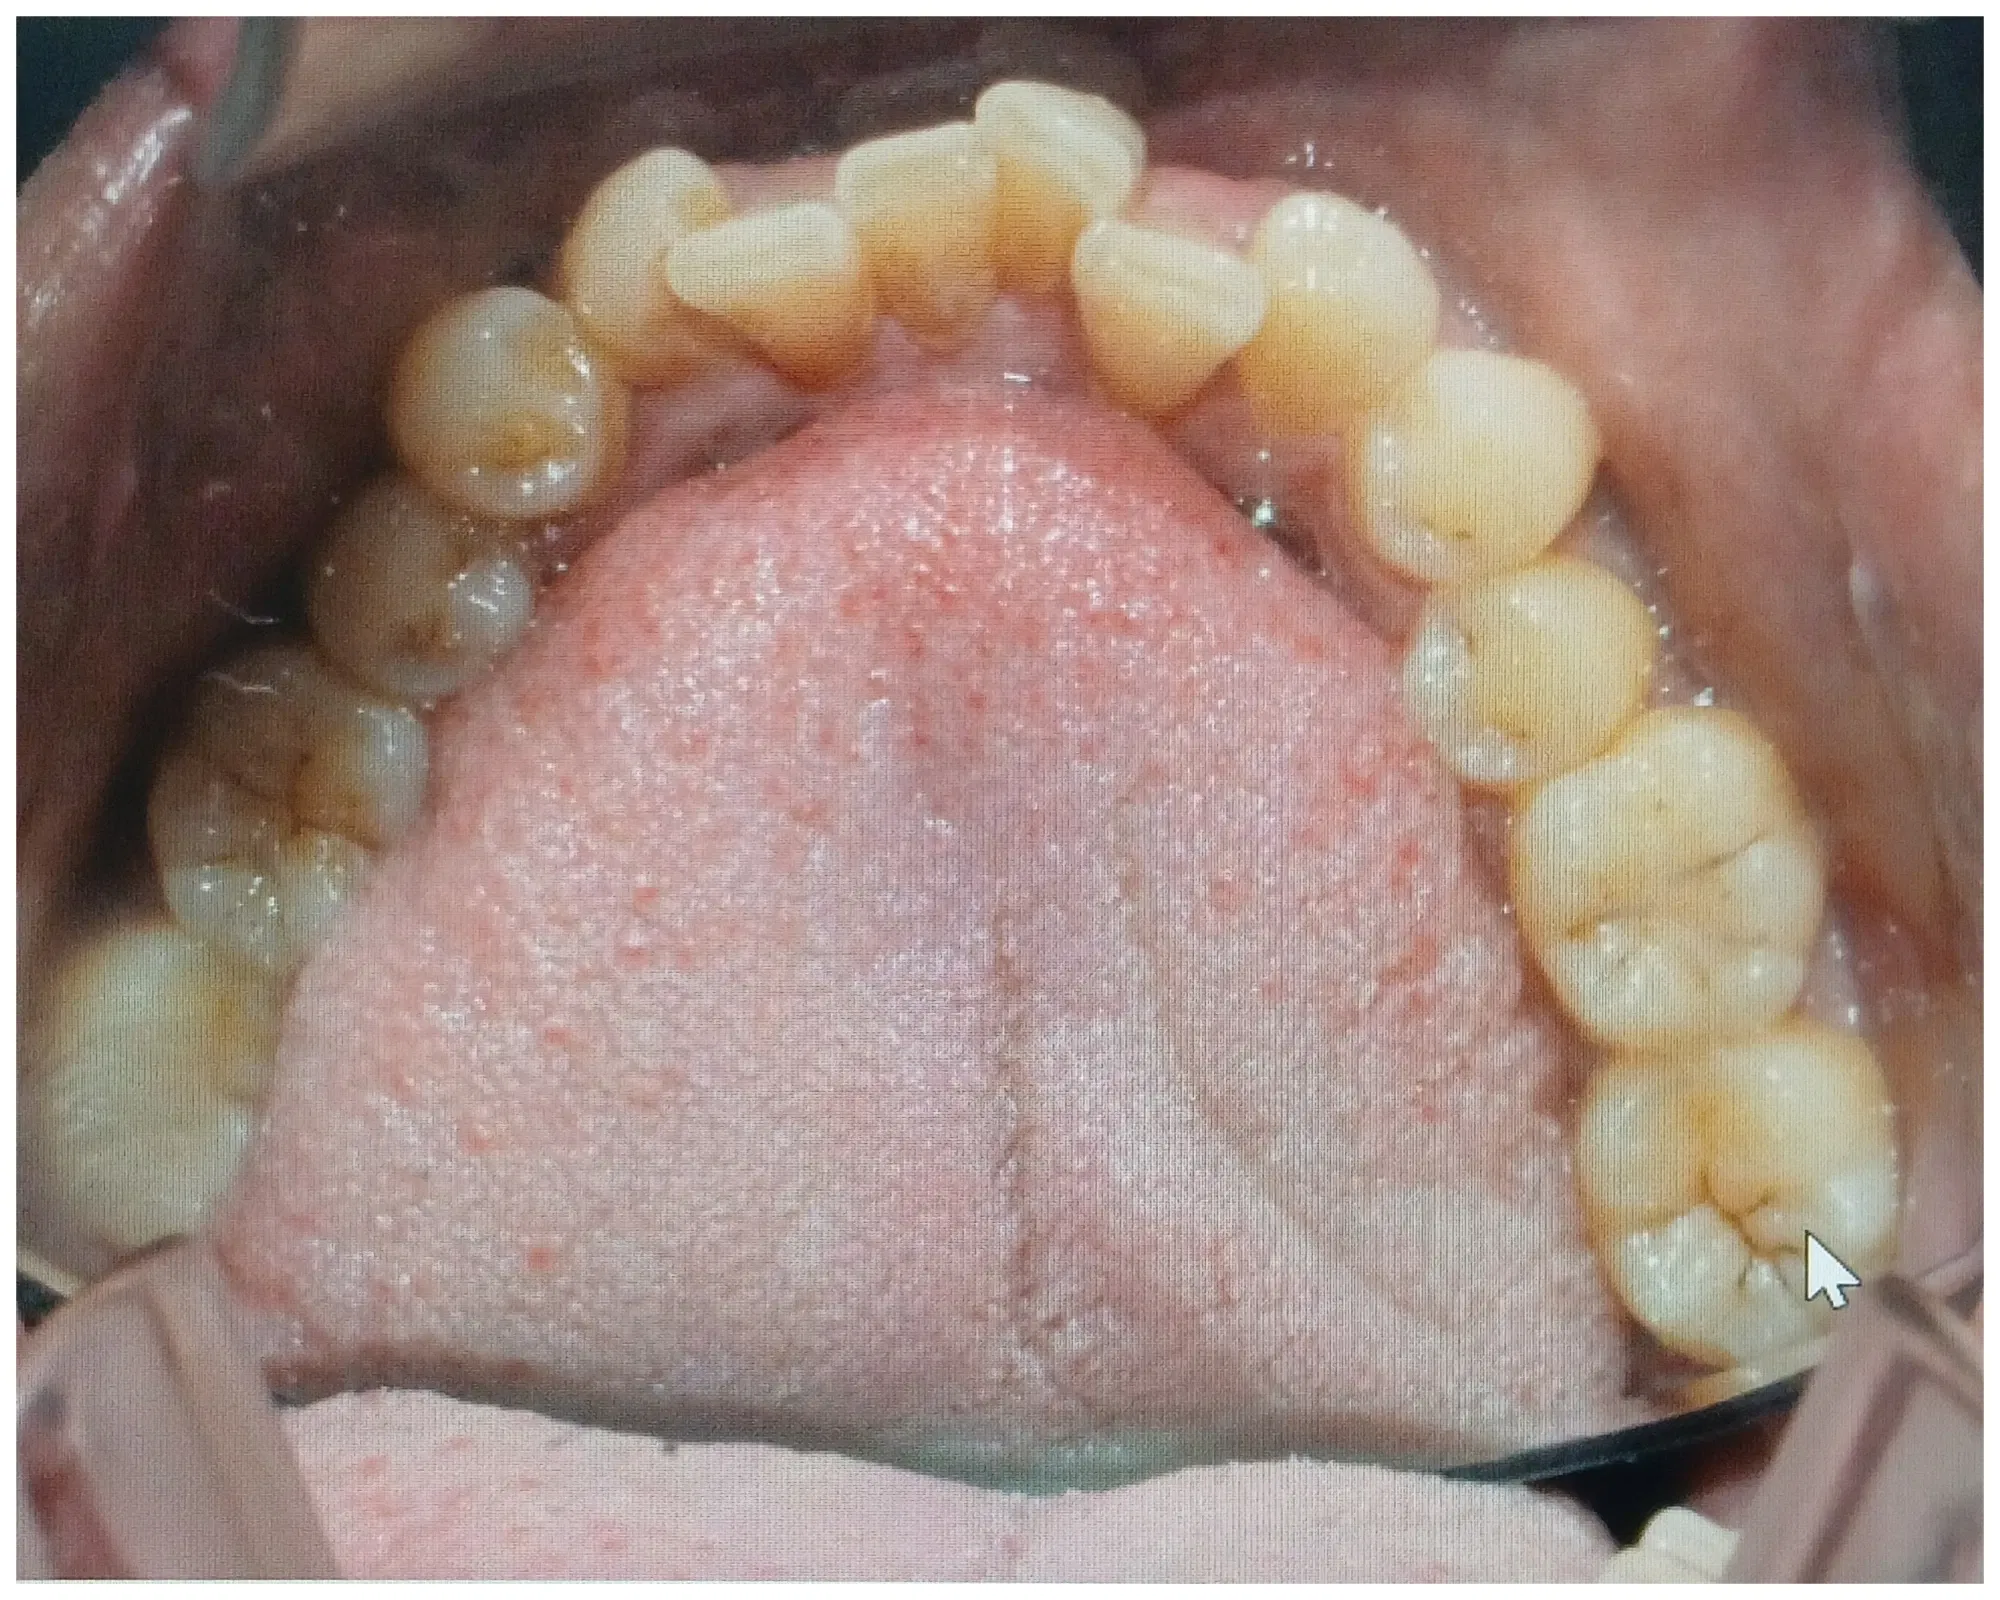

el apiñamiento dental es una condición donde los dientes no tienen el suficientemente espacio para poder tener una oclusión perfecta esto se puede deber a que hay poco espacio los maxilares al momento de la erupción dentaria de los dientes permanentes puede tener distintas causas las tres principales son hábitos con Factor genético y el tipo de alimentación.

Podemos aplicar brevemente cada uno de ellos los hábitos tenemos como el hábito de respirador bucal o el destrucción digital de chupar deo o el del chupete o chupón no puede causar una malformación en desarrollo de los maxilares que los puede contraer por lo tanto al momento del recambio dentario cuando vienen los dientes permanentes pues son mucho más grandes y el espacio está reducido en cuanto a la alimentación tenemos que en tiempo de nuestros abuelos y bisabuelos pues la alimentación de ellos era mucho más magra la era una comida menos refinada por lo tanto ellos tenían que utilizaban más la mandíbula y los dientes para triturar para mascar para rasgar ya hoy en día Todo se le da listo picado al niño Entonces no hace ningún tipo de esfuerzo para estimular el desarrollo tanto óseo como muscular lo que provoca también contracción en los maxilares.

Por último y él no menos importante es una condición genética donde un niño puede heredar el tamaño óseo del papá y el tamaño dental de la mamá o viceversa aquí eso también contribuye a que de repente tengamos un maxilar pequeño en dientes muy grandes o maxilar grande diente muy pequeño dependiendo de la genética o de la herencia que deje cada uno los progenitores.

En cualquiera de los casos pues hay que realizar un tratamiento ortopédico si son niños y tratamiento ortodoncia en el futuro para alinear los dientes y nivelarlos y hacerles el espacio suficiente en el arco dental para tener una mordida excelente para no tener trauma de oclusión ni alteraciones en el artículo Centre por mandibular esto cuando entre más temprano se puede realizar este tipo de tratamiento pues mucho mejor cualquier duda comentario pregunta o interconsulta estoy muy dispuesta alegre de poderte ayudar y responder.